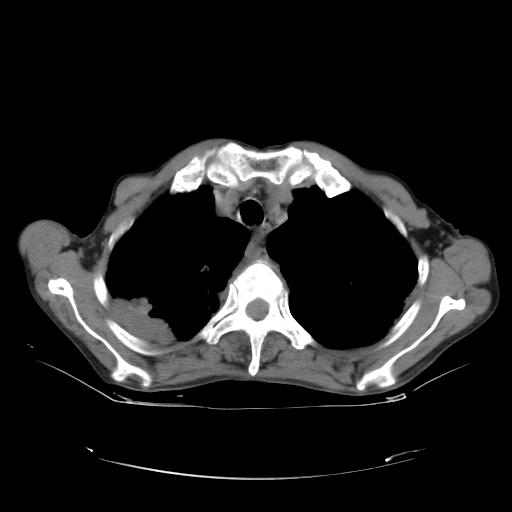

女,72岁,咳嗽一周余,突发右下肢无力二天。

pe:bp-140、80mmhg,精神可,伸舌居中,右上肢肌力正常,右下肢肌力0级,巴氏征+

来院做头颅+胸部ct平扫

胸部病变平扫35hu,增强强化至70hu

这个病人首先是胸部病变的定位到底是肺内还是肺外。仔细观察块影位于胸膜下,与胸膜间有透亮带,且近端血管未见明显推移而是引流样改变,形态分叶,说明这个病灶位于肺内胸膜下。很可能是腺癌,腺癌最易致颅内高密度转移灶。局部胸膜有侵犯。

本例颅内见多发大小不等高密度灶,有强化及水肿;另外,胸锁关节层面可能是第四胸椎及右侧肋骨起始部骨质欠连续,椎旁软组织肿胀,建议调骨窗观察。

诊断:右下肺癌伴颅内、胸椎、肋骨转移可能性最大。